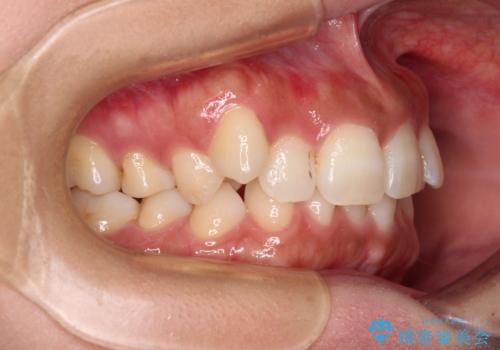

上顎小臼歯を抜歯するかどうか悩みましたが、八重歯の後方に失活歯があること、治療前に上顎正中が概ね人中に合っていることから、右上第二小臼歯を抜歯することとしました。

片側での抜歯であると、正中が抜歯した方向にずれていくため、左上の奥歯を遠心移動させる目的でアンカースクリューと補助装置を併用した上で、ワイヤー装置にて矯正治療を行うこととしました。

上顎の正中位置をほぼ保った状態で、綺麗に仕上げることができました。